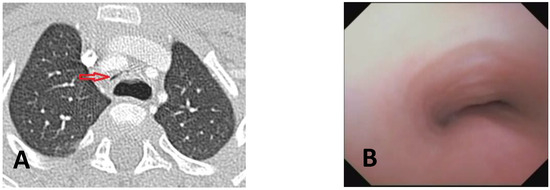

Diagnosis, Treatment, and Follow-Up of Tracheo/Bronchomalacia in Children: The Italian Multicenter Experience

by Angelo Florio, Michele Ghezzi, Francesca Rizzo, Paolo Del Greco, Katia Perri, Fabio Antonelli, Annalisa Gallizia, Francesco Santoro, Elena Ribera, Francesco Macchini, Michele Torre, Francesco Donati, Federica Lena, Vittorio Guerriero, Paola Borgia, Valerio Gentilino, Roberto D’Agostino, Federica Porcaro, Alessio Conte, Duino Meucci, Roberto Baggi, Michele Gaffuri, Pietro Salvati and Oliviero Saccoadd Show full author list remove Hide full author list

Children 2025, 12(11), 1511; https://doi.org/10.3390/children12111511 - 7 Nov 2025

Background: In pediatric age, the central airways are more flexible and mobile, with tracheal and bronchial walls easily tending to collapse, allowing partial or complete occlusion of the lumen: a situation described as tracheobronchomalacia (TBM). This is a condition that causes an increase [...] Read more.

Background: In pediatric age, the central airways are more flexible and mobile, with tracheal and bronchial walls easily tending to collapse, allowing partial or complete occlusion of the lumen: a situation described as tracheobronchomalacia (TBM). This is a condition that causes an increase in intrathoracic pressure that may accentuate airway collapse, and a biphasic or barking cough appears. Objectives: Although TBM is relatively frequent in pediatric age, the diagnostic criteria and subsequent treatment do not follow well-standardized criteria and often vary from pediatric center to center. Therefore, there is a need to standardize diagnostic procedures and the resulting medical or surgical treatments. Methods: We therefore organized a day of meetings to talk about TBM, inviting all Italian pediatricians and pediatric surgeons who diagnose and treat patients with this pathology on a daily basis. Results: This work, collecting all the meeting interventions, is a compendium that deals with all aspects of TBM, emphasizing the most correct criteria to diagnose and therefore best treat each pediatric patient with this clinical condition. We give particular emphasis to the need to perform static and dynamic videobronchoscopy (S/DVBS) to verify the patency of the tracheal lumen, so as to evaluate the severity of TBM. Conclusions: this work deals with TBM in all its diagnostic and treatment aspects and can be a valid help for all pediatricians who treat these patients. Full article

Show Figures

Figure 1